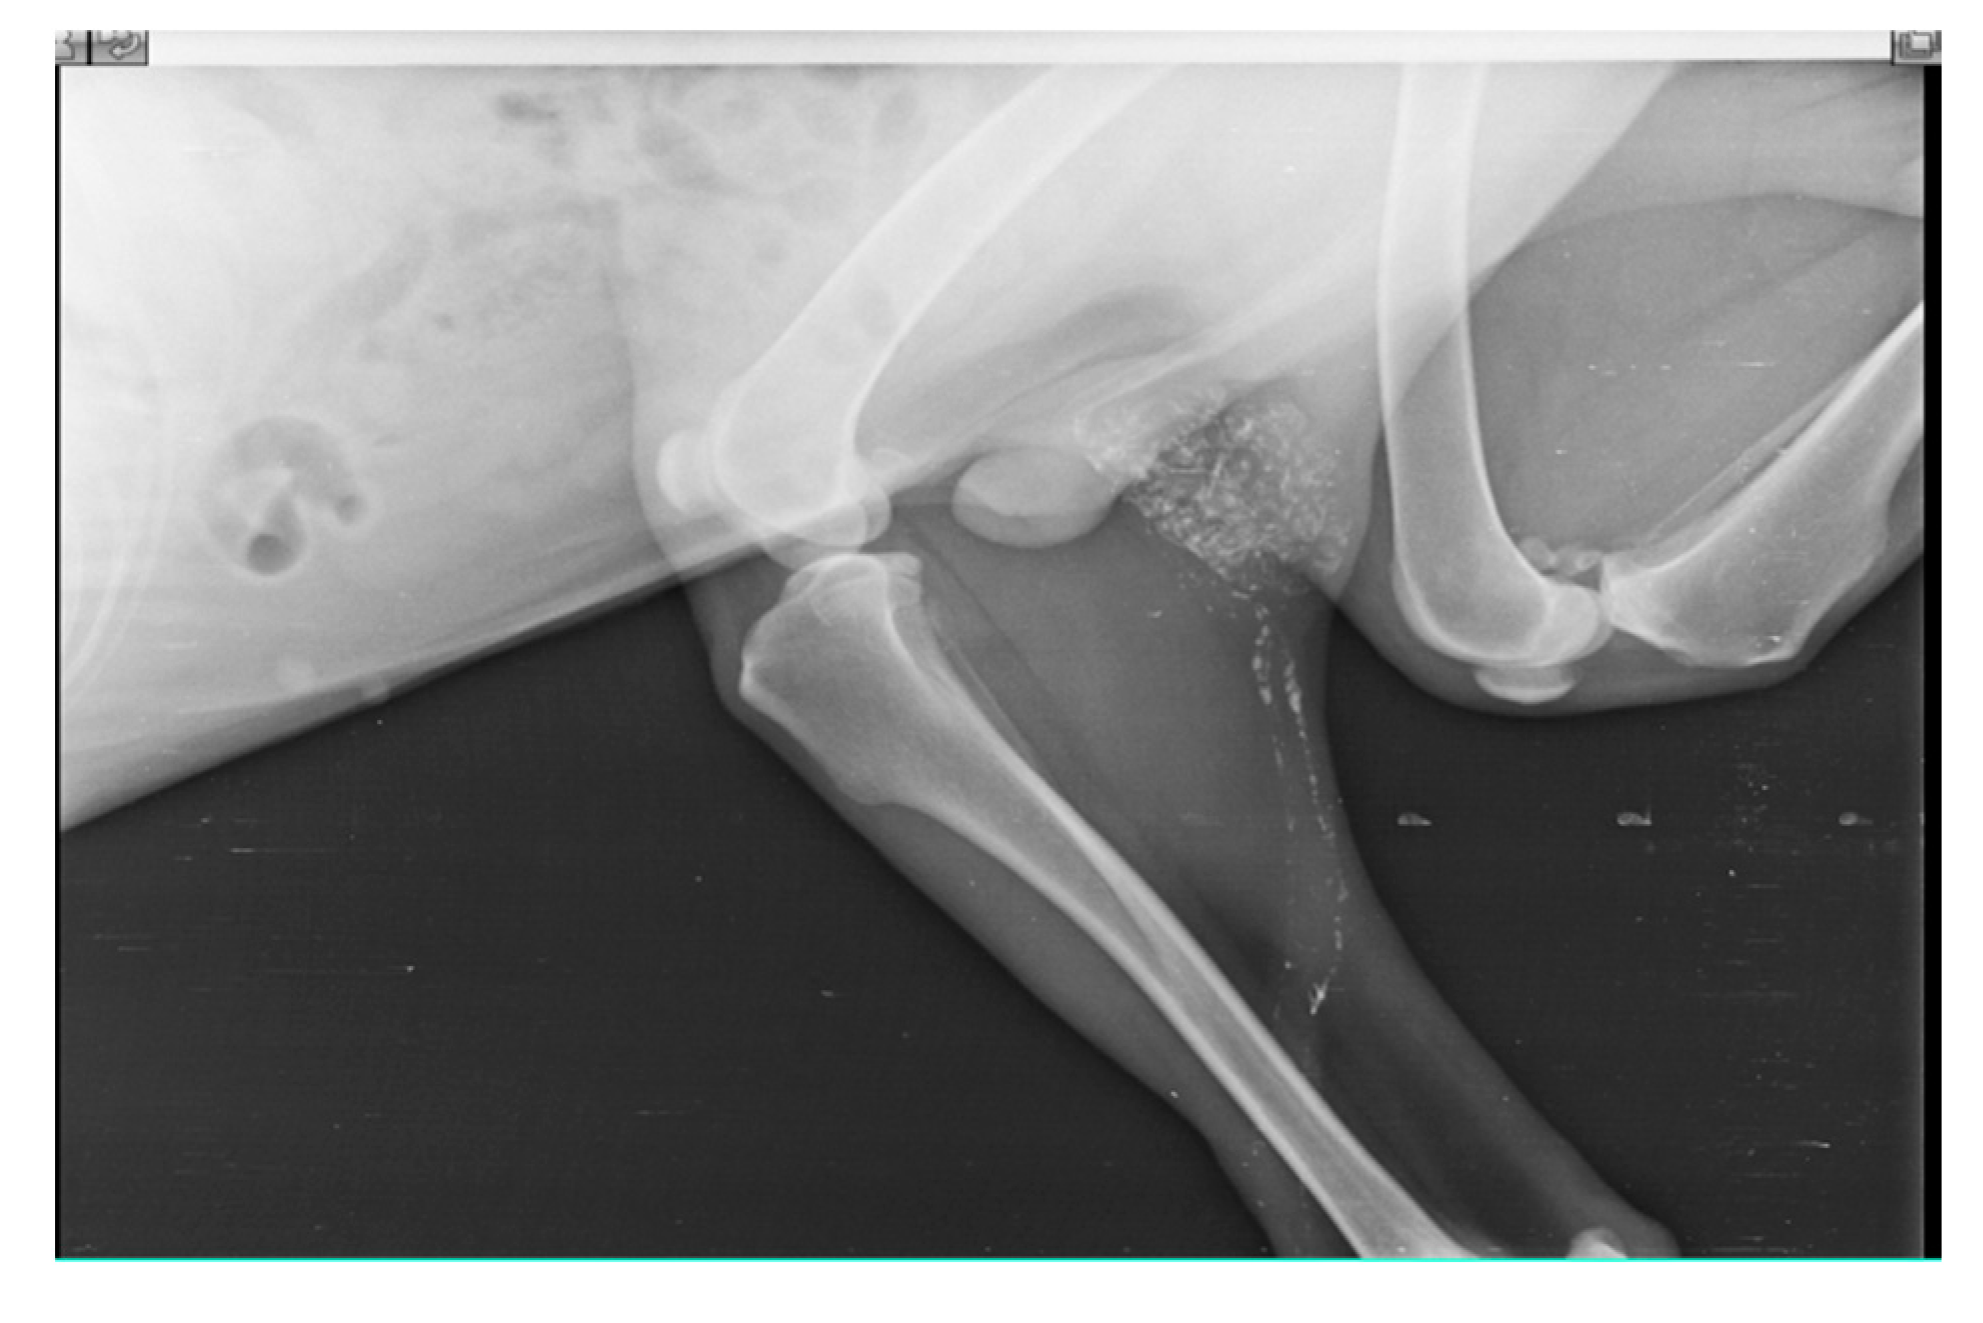

SLN was detected in histiocytic sarcoma (n=4) and buttock sarcoma (n=3) only, and not localized in other soft tissue sarcoma (n=7) (lipoma, liposarcoma, infiltrative lipoma, cavernous hemangioma and cutaneous fibrosarcoma). Indirect CT lymphography with iohexol injection in histiocytic sarcoma detects inguinal LN as SLN (Figure 7) and miLN as a second-tier node within 2 min, and the inguinal node is found metastasis-free on cytology and biopsy.

Figure 7. Inguinal LN as SLN in histiocytic sarcoma detected through indirect CT lymphography with iohexol.

Preprints 77141 g007

IL with Lipiodol in recurrent buttock sarcoma (operated six times) detects lymphatic flow to right inguinal LN only after 24 hours and to miLN after 48 hours as shown in Fig. 8. The opacity was noticeable upto 28 days of injection.

Figure 8. Inguinal LN (plain arrow) as SLN for buttock sarcoma detected through IL with Lipiodol and miLN (solid arrow) is the second-tier node.

Preprints 77141 g008